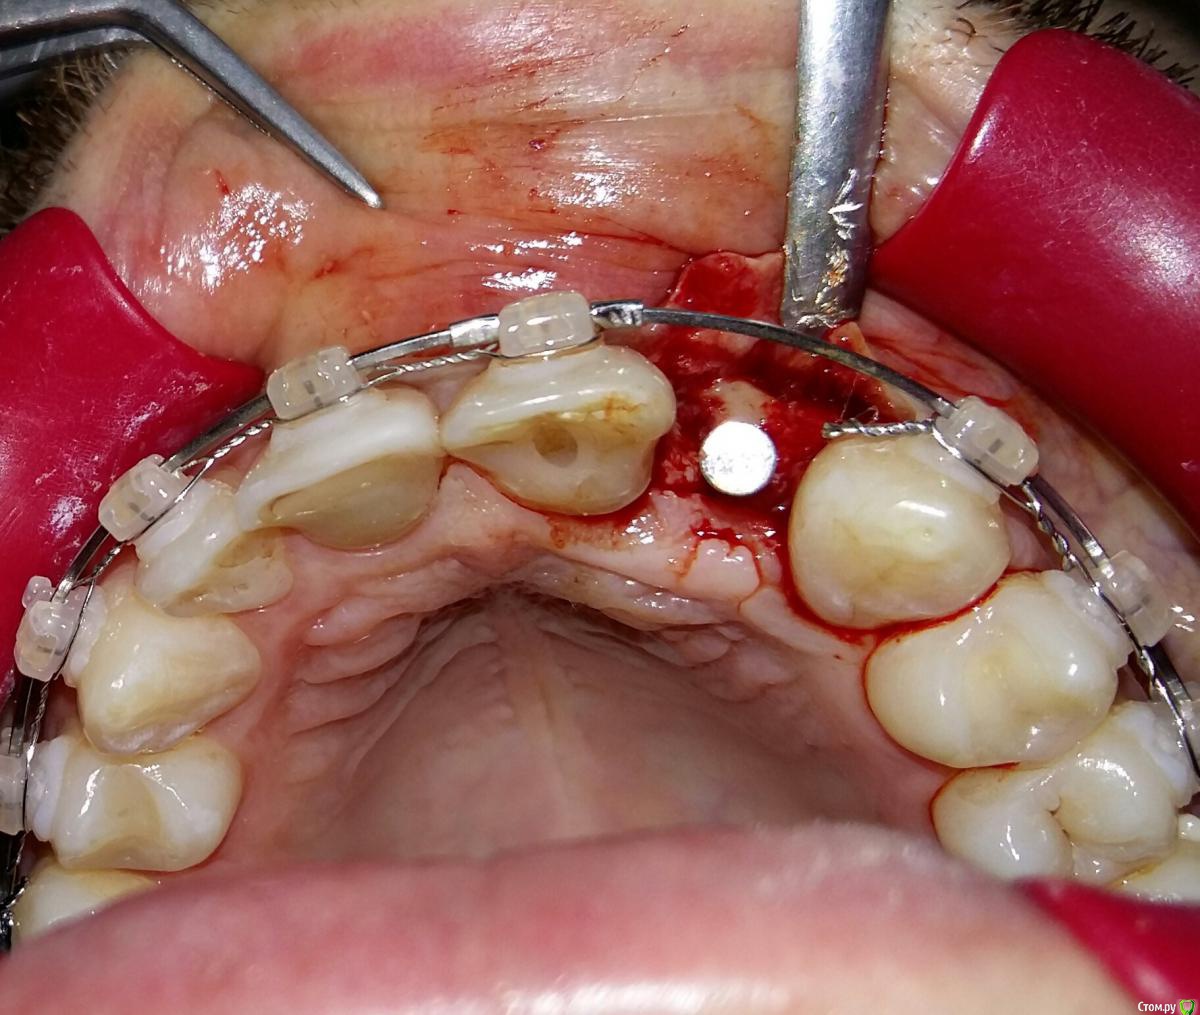

Kostoprav Опубликовано 8 июля, 2015 Поделиться Опубликовано 8 июля, 2015 ИЗНАЧАЛЬНАЯ СИТУАЦИЯ ПОЛУЧИЛОСЬ сори что нет фото до имплантации. Блок взял с тела челюсти, фиксировал двумя винтами (во время имплантации выкрутил только один), присыпал gen os, укрыл дермой-получил заметный прирост слизистой) имплант альфадент 3,75х11,5 2 Ссылка на комментарий

Kostoprav Опубликовано 8 июля, 2015 Автор Поделиться Опубликовано 8 июля, 2015 Видно что блок прирос. ЗдоровоОстальное оценить сложноМне нравится положение импланта в плане оси.Но уровень заглубления не ясенТакже не видно прироста десныВ общем мало данных для оценкиНо опять же вам именно она и нужна?по вестибюлярной поверхности заглубил приблизительно на 1мм с небной больше получилось. слизистая по сравнению с первым разом значительно толще стала, доказать к сожалению не могу так как не делал фото(: я выложил этот пост не только ради оценки, может кому из начинающих данный случай сгодиться 3 Ссылка на комментарий